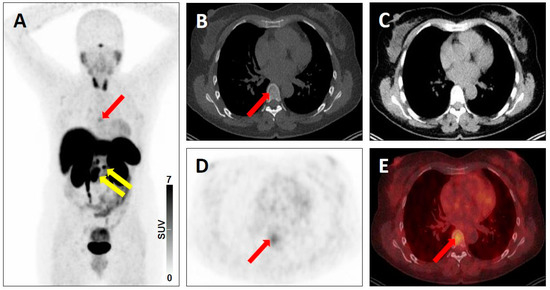

| 3D | - Single liver lesion without SSTR expression but finding on conventional imaging [20] - Modest/No radiotracer uptake in the primary of the lung, with intense radiotracer uptake on 2-deoxy-2-18F-fluoro-d-glucose PET two weeks later [18] | - Prostate cancer (PC) of neuroendocrine origin [19] - Non-radiotracer-avid lung nodule in a patient with biochemically recurrent PC [19] | |